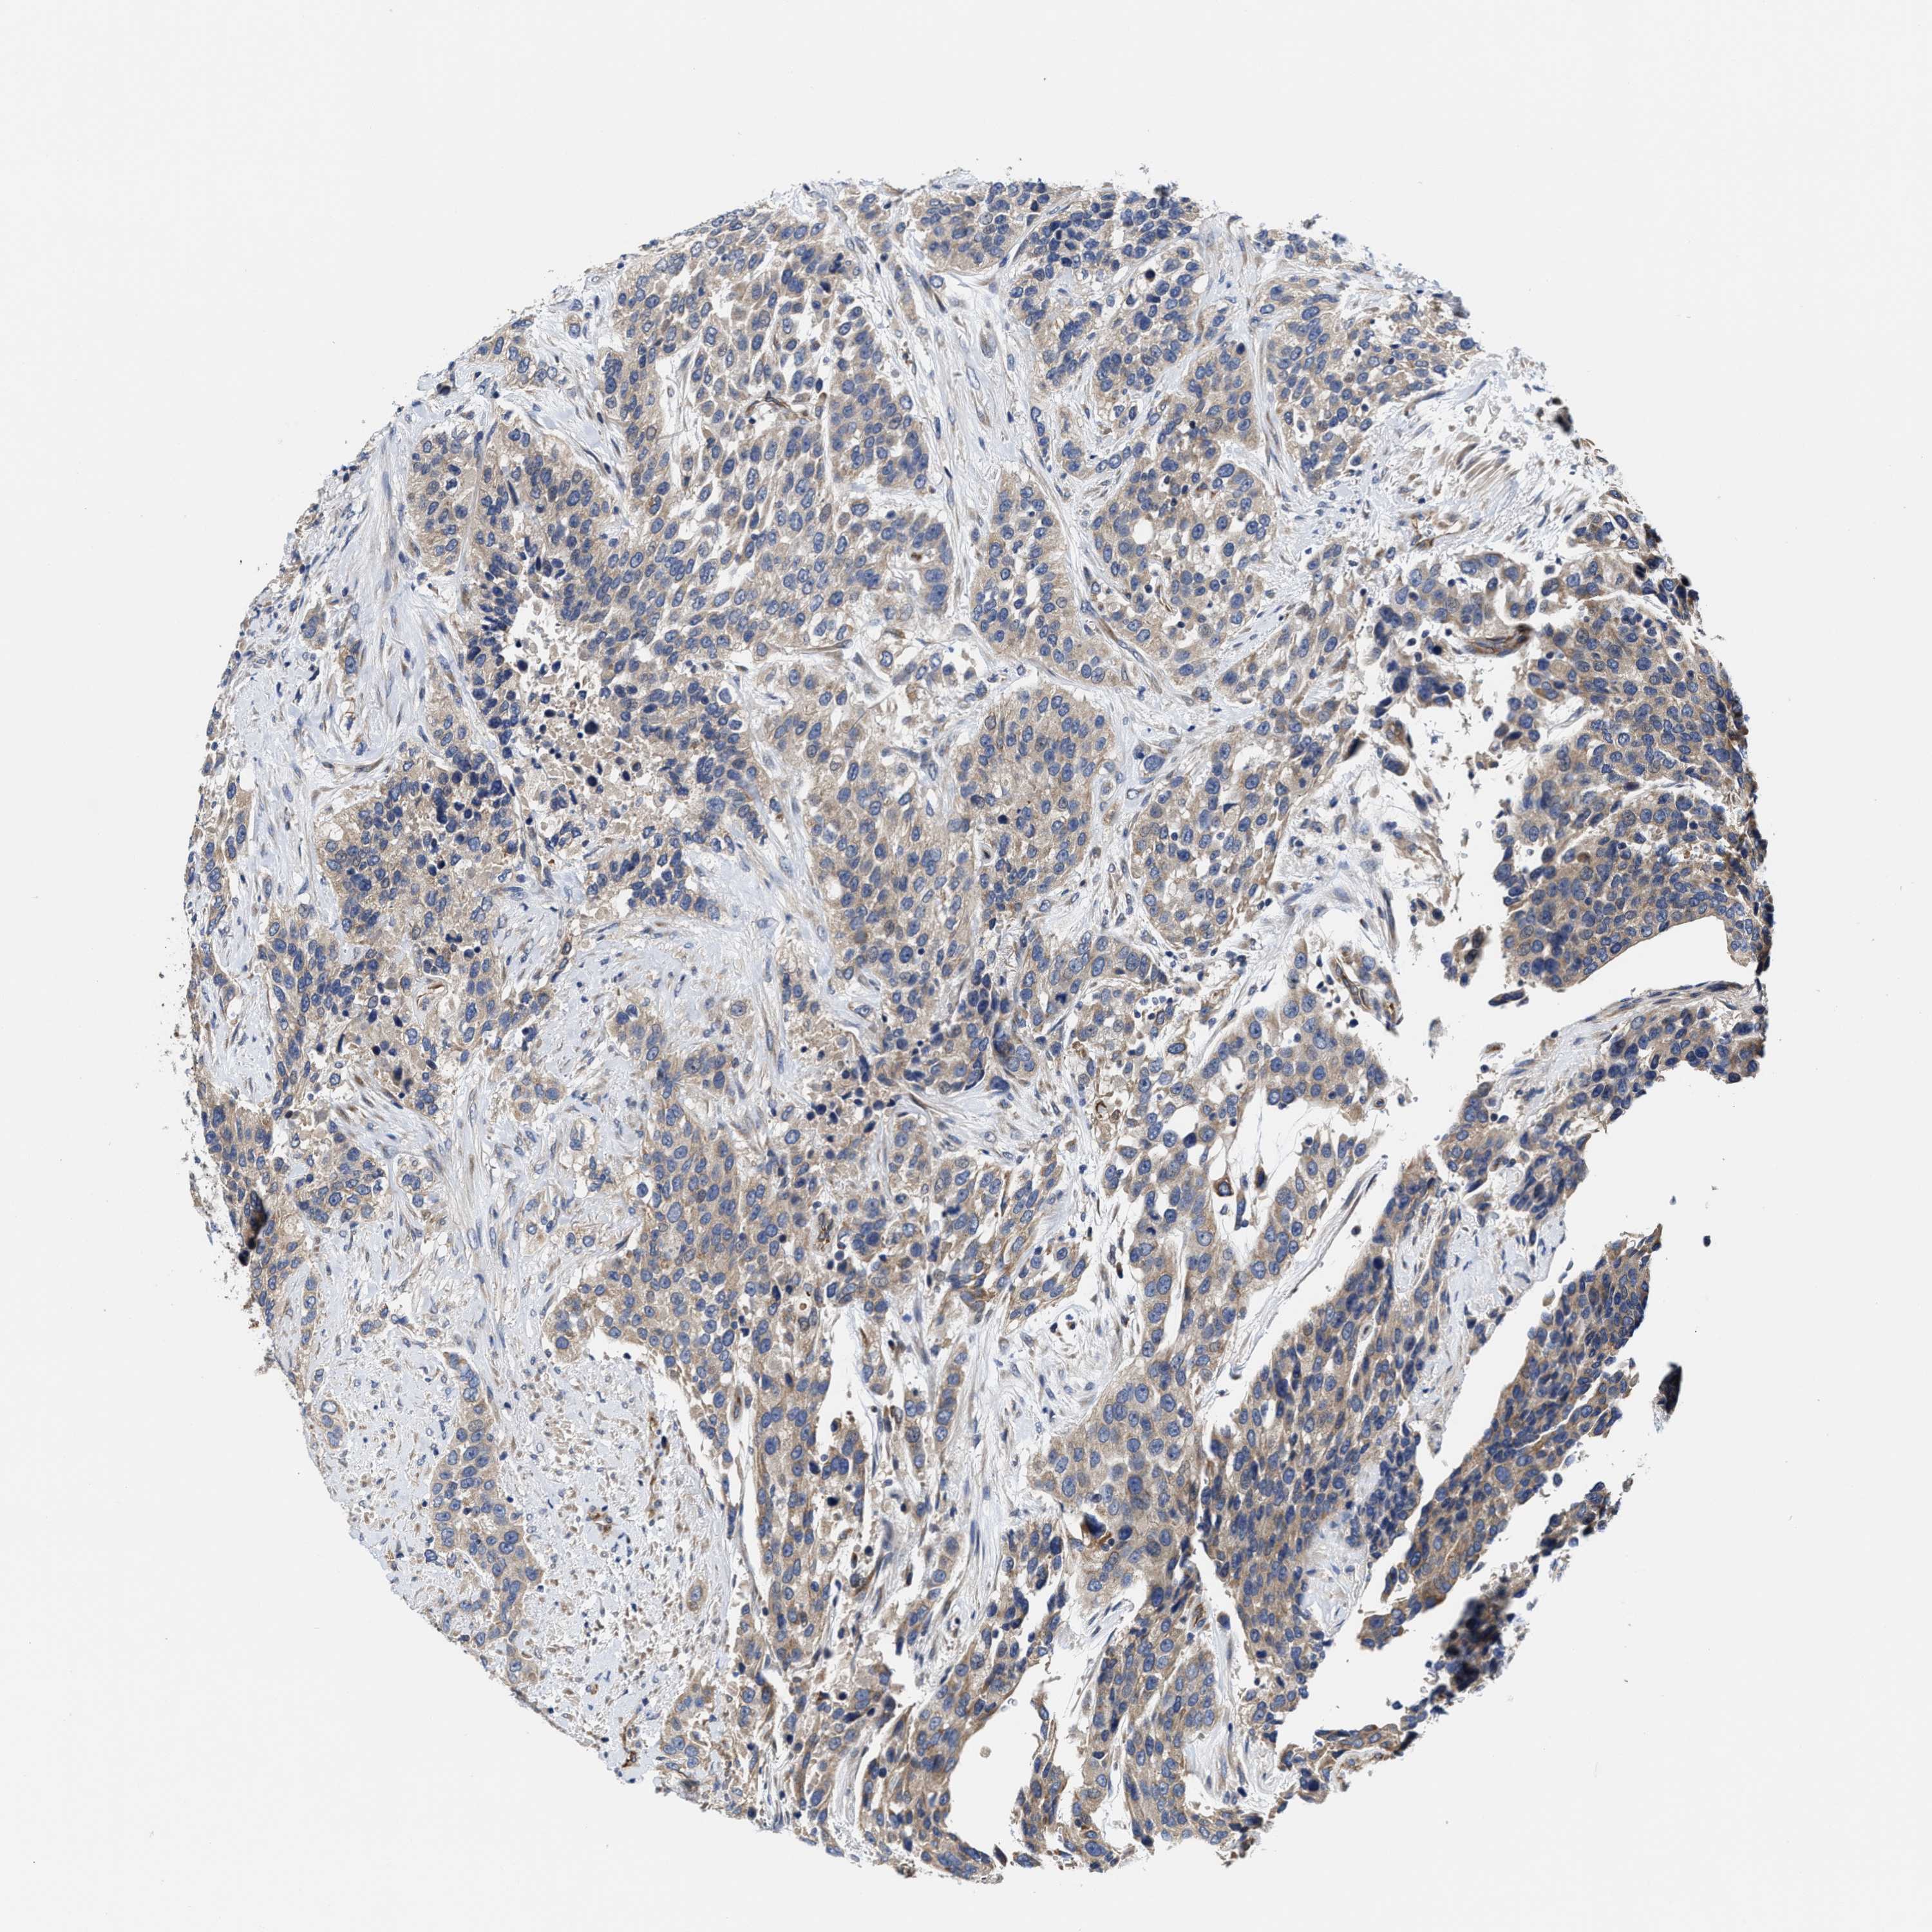

UROTHELIAL CANCER - Protein expressioni

A mouse-over function shows sample information and annotation data. Click on an image to view it in a full screen mode. Samples can be filtered based on level of antibody staining by selecting one or several of the following categories: high, medium, low and not detected. The assay and annotation is described here.

Note that samples used for immunohistochemistry by the Human Protein Atlas do not correspond to samples in the TCGA dataset.

Antibody stainingi

Antibody staining in the annotated cell types in the current human tissue is reported as not detected, low, medium, or high, based on conventional immunohistochemistry profiling in selected tissues. This score is based on the combination of the staining intensity and fraction of stained cells.

Each image is clickable and will lead to virtual microscopy that enables deeper exploration of all samples and also displays staining intensity scores, fraction scores and subcellular localization as well as patient and tissue information for each sample.

Antibody HPA019805

Antibody HPA020599

Antibody CAB004605

Staining

High

Medium

Low

Not detected

Intensity

Strong

Moderate

Weak

Negative

Quantity

>75%

75%-25%

<25%

None

Location

Nuclear

Cytoplasmic/membranous

Cytoplasmic/membranous,nuclear

Urothelial carcinoma, Low grade

Urothelial carcinoma, High grade